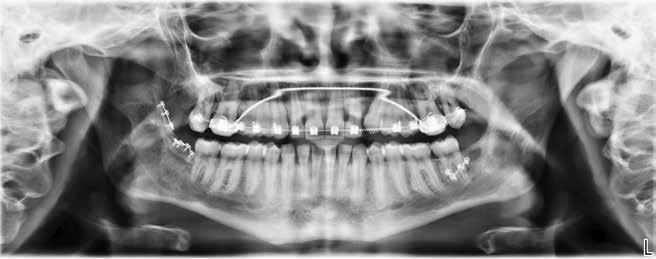

Zygomaimplantater anvendt i særlige patienttilfælde / 574

Vi ser på anvendelsen af zygomaimplantater, som er en mulighed hos patienter, hvor knogleopbygning ikke er en mulighed.

Fig. 1. Radiologisk sekvens efter en rodperforation i forbindelse med en stiftpræparation i en underkæbemolar (-6). A. Røntgenbillede før rodbehandling. Rodkanalmorfologien viser, at den distale rod har to adskilte rodkanaler (pil). B. Rodbehandling afsluttet og kontrolleret. C. Initial mekanisk fjernelse af rodfyldning. D. Efter mekanisk fjernelse af rodfyldning ses en retningsafvigelse i forhold til den nederst beliggende rodfyldning. E. En midlertidig fyldning af rodkanalen viser rodperforationen (pil). Der er indhentet patientsamtykke til visning af røntgenbilleder.

Fig. 1. Radiologic sequence after root perforation in connection with mechanical preparation of a post in a mandibular molar (-6). A. Radiograph before the procedure. The morphology of the root canal shows that the distal root has two separate root canals (arrow). B. Procedure completed and controlled. C. Initial mechanical removal of root filling. D. After the mechanical removal of root filling the direction of the drill deviates from the lowest part of the root filling. E. A temporary filling of the root canal shows the root perforation (arrow). The pictures are used with the permission and consent of the patient.